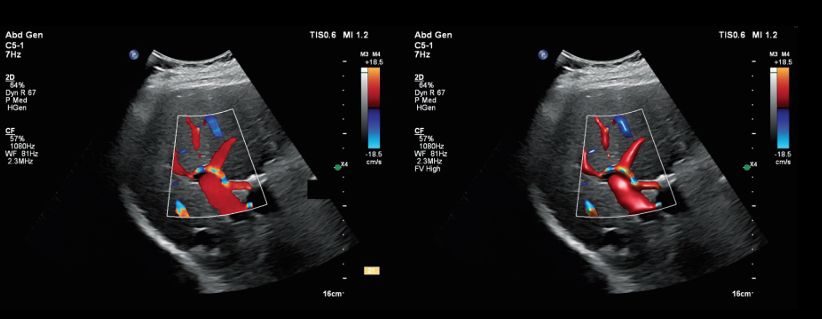

Traditional Color Doppler imaging can sometimes make it challenging to distinguish adjacent vessels or clearly define vessel boundaries—especially when flow direction is similar or anatomy is complex. Flow Viewer addresses these challenges by leveraging both Doppler velocity and Doppler power data to:

For example, the image below demonstrates how Flow Viewer enables clearer differentiation between the portal vein and hepatic artery—even when vessels are closely positioned and share similar flow direction.

Color Doppler image of the portal vein and hepatic artery. Right: Flow Viewer version of the image on the left (applied in post-processing).

Abdominal and transplant imaging

In complex cases such as liver transplant evaluation, Flow Viewer has demonstrated measurable improvements:

These gains can be particularly valuable when assessing small or difficult-to-visualize vessels.